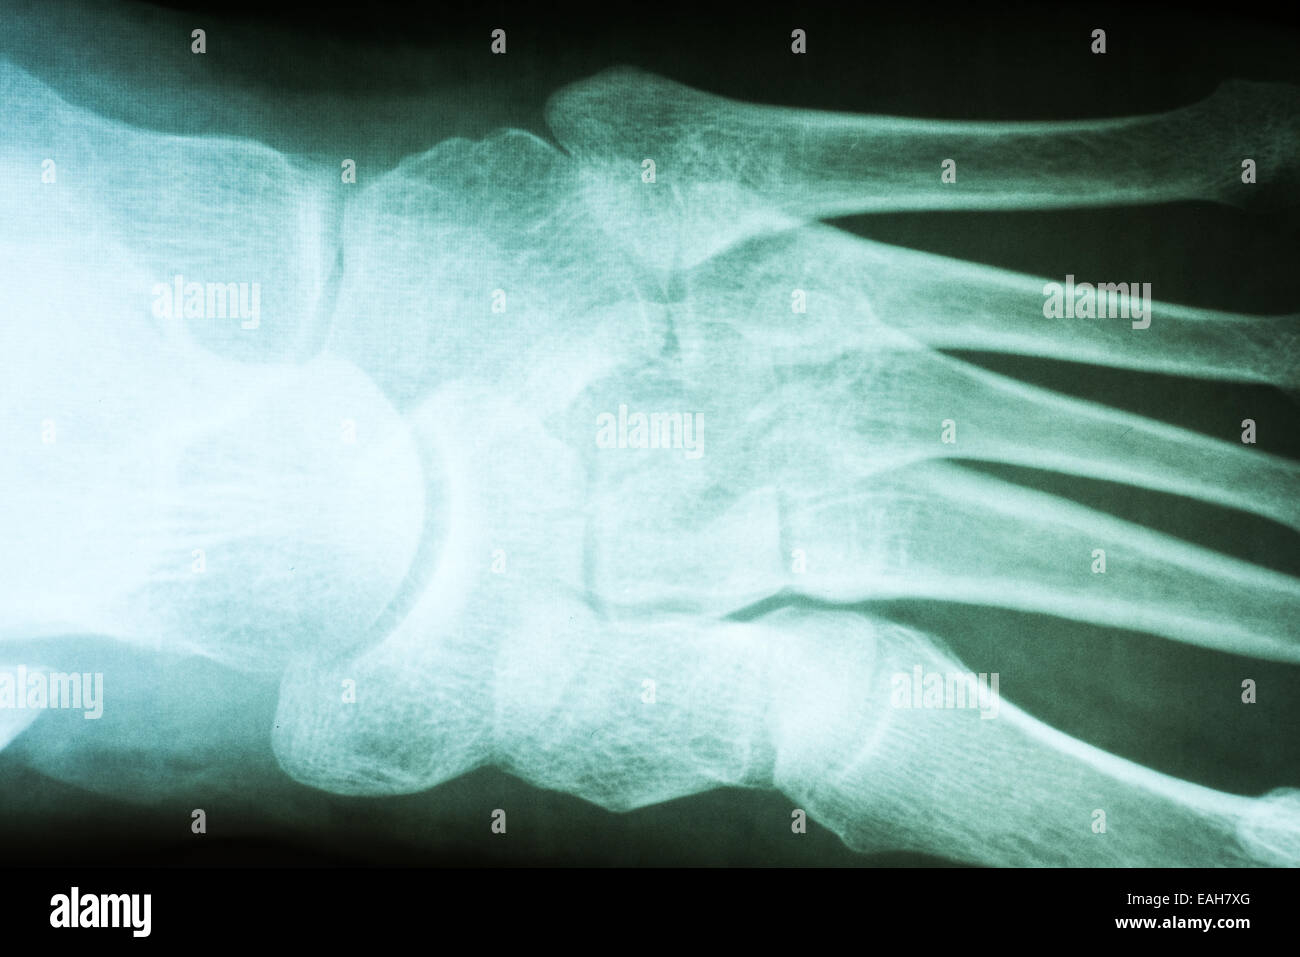

RMBR4J1F–X-ray pied d'une femme de 53 ans qui a frappé son pied et s'est fracturé la phalange proximale de son petit orteil